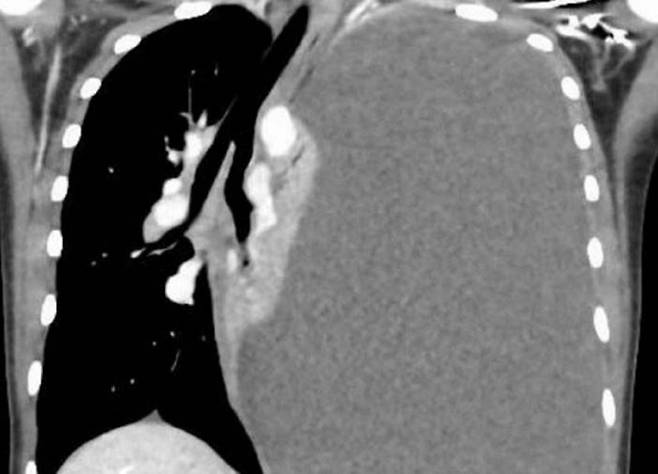

지난해 4월엔 14세 여학생이 호흡곤란과 함께 기침·피가 섞인 가래가 발생해 부산대 병원 응급실에 실려 왔다. 특별한 질환은 없었는데, 다만 가끔 가족과 민물 게를 먹었고 응급실에 오기 3개월 전 마지막으로 민물 게를 먹었다고 한다. 흉부 엑스레이 검사 결과 폐 흉막에 다량의 삼출액을 발견하고 삼출액을 즉시 빼냈다. 추가 검사 결과 기관지 폐포에서 폐흡충 알이 검출돼 폐흡충증 확진 판정을 받았다. 구충제를 경구 투여해 증상이 완화됐지만 여전히 폐가 쭈그러드는 ‘무기폐’ 상태가 지속돼 흉막 박피술을 진행했다.

폐흡충증은 우리나라에서 1960년대까지 비교적 흔한 질환이었지만 현재는 거의 보고되지 않는다. 민물 게를 이용한 음식 섭취에 의해 산발적으로 발생한다. 사람의 폐에 주로 자리를 잡고, 1.5~2.5cm 크기의 주머니를 형성해 그 안에 알을 낳는다. 마른 기침, 갑작스러운 호흡곤란, 복통 등의 증상이 나타나는데 구충제 프라지콴텔을 쓰면 대부분 제거된다.